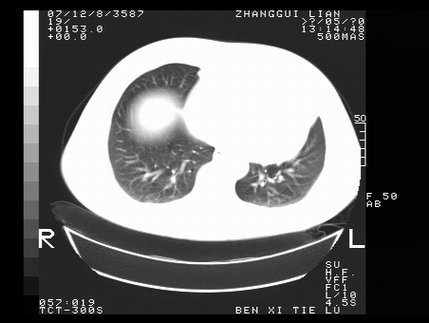

标题: CT10817:女,46,胸疼,无其他病史 [打印本页]

标题: CT10817:女,46,胸疼,无其他病史

左侧上纵隔旁团块影,部分植入纵隔,与纵隔界限不清,另:左肺门明显见团块,气管隆突前方见肿大淋巴结。考虑:左上肺纵隔型肺癌伴左肺门及纵隔淋巴结转移!

首先考虑左侧中央型肺癌伴阻塞性肺炎、纵隔内、弓旁淋巴结转移可能性大(纵隔窗调的欠佳)

1左上肺中心型肺癌伴左肺上叶不张2主动脉弓旁淋巴结转移3左下肺炎症

1 左侧中央型肺癌伴阻塞性肺炎 2 左肺门及纵隔淋巴结转移!3两侧胸腔及心包积液.

左侧胸廓塌陷,纵隔向左侧移位,左上肺不张。